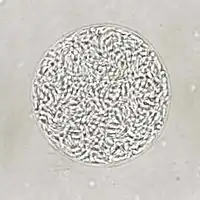

| Giemsa stained T. gondii tachyzoites, 1000× magnification | |

Tachyzoites

Motile, and quickly multiplying, tachyzoites are responsible for expanding the population of the parasite in the host.[47][30]: 19 When a host consumes a tissue cyst (containing bradyzoites) or an oocyst (containing sporozoites), the bradyzoites or sporozoites stage-convert into tachyzoites upon infecting the intestinal epithelium of the host.[30]: 359 During the initial acute period of infection, tachyzoites spread throughout the body via the blood stream.[30]: 39–40 During the later, latent (chronic) stages of infection, tachyzoites stage-convert to bradyzoites to form tissue cysts. To survive in the host, tachyzoites manipulate the immune response by injecting the contents of rhoptries into host cells. This seems to be vital for their survival, as knock-out strains of T. gondii are unable to inject hosts with rhoptries have been shown to be avirulent in vivo.[29]